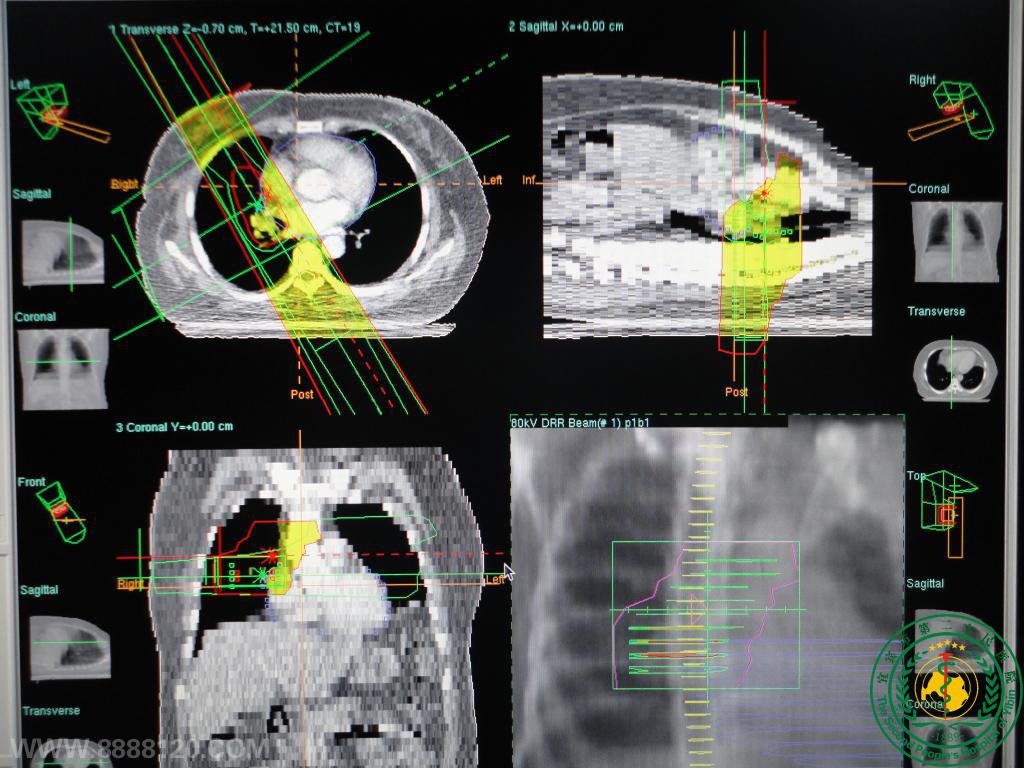

NPC  3DCRT靶区、射野、射束及DVH